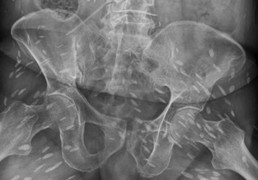

Quá nhiều trứng sán trong người khiến não của người đàn ông bị ảnh hưởng, gây ra hiện tượng mất trí nhớ và đi lại khó khăn.